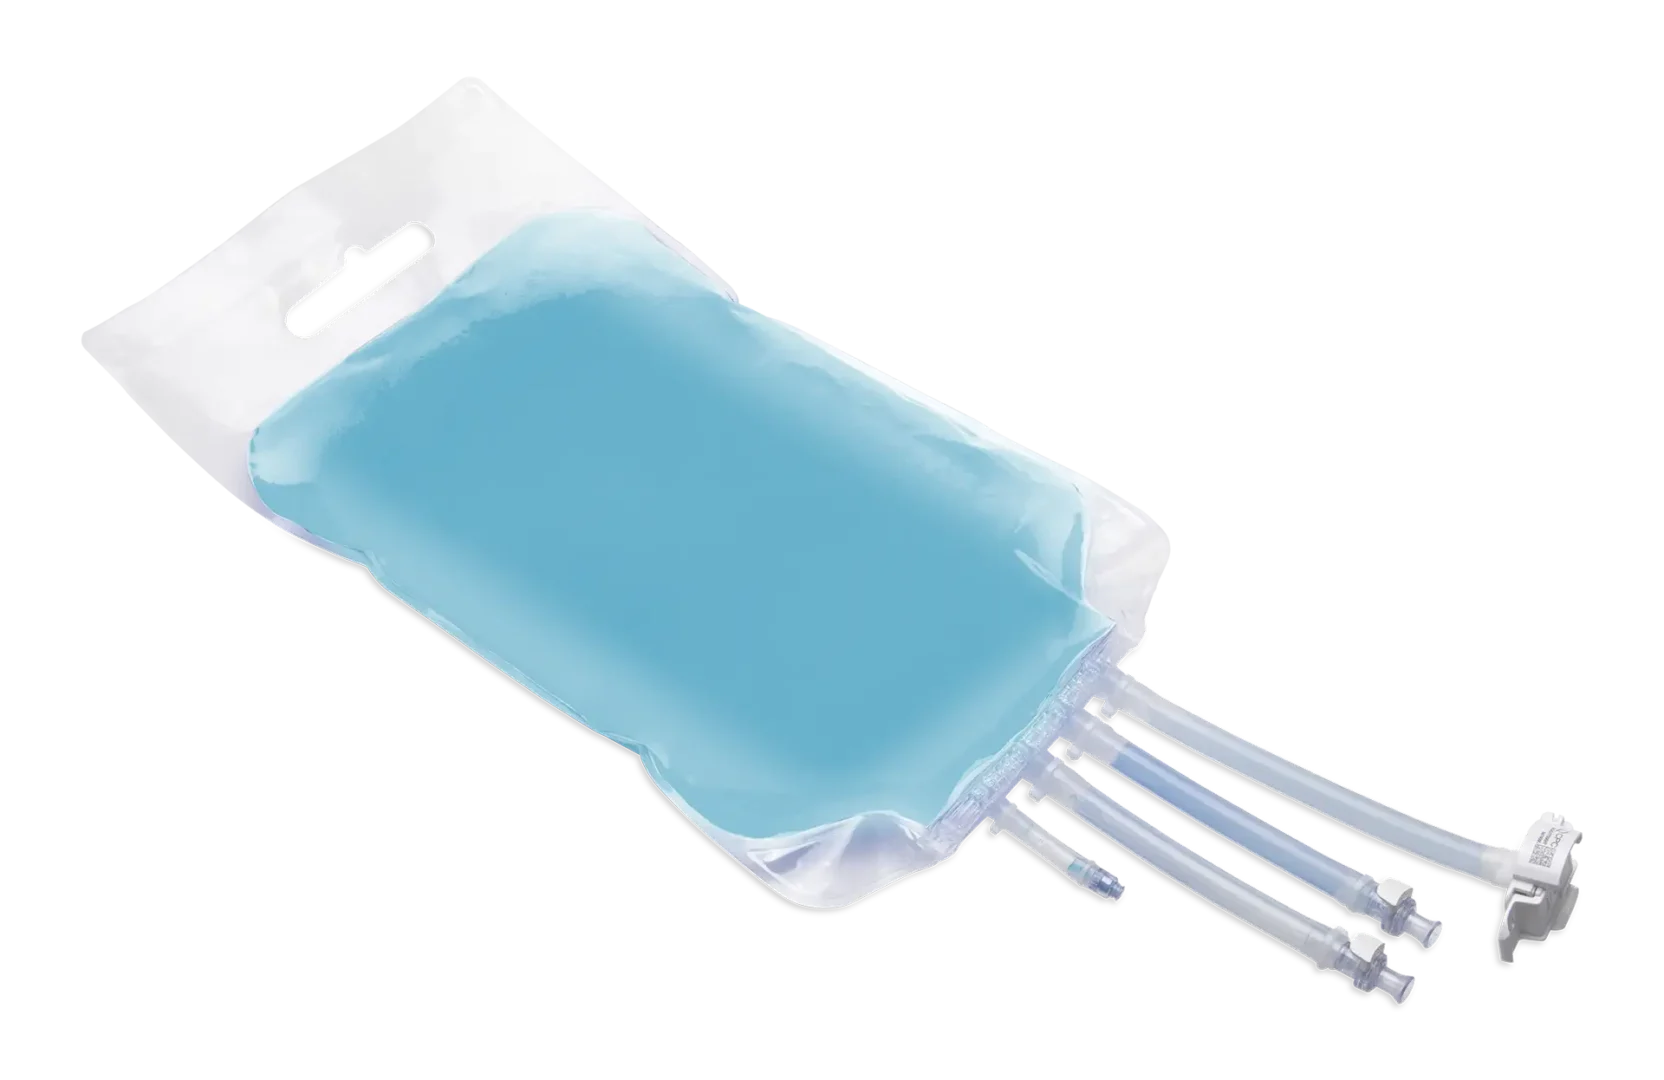

The perfect partner in the production of TPN, blood treatment, drainage and single use bags.

Valmed srl is the ideal partner, guaranteeing experience and know-how in the production of finished or semi-finished medical devices.